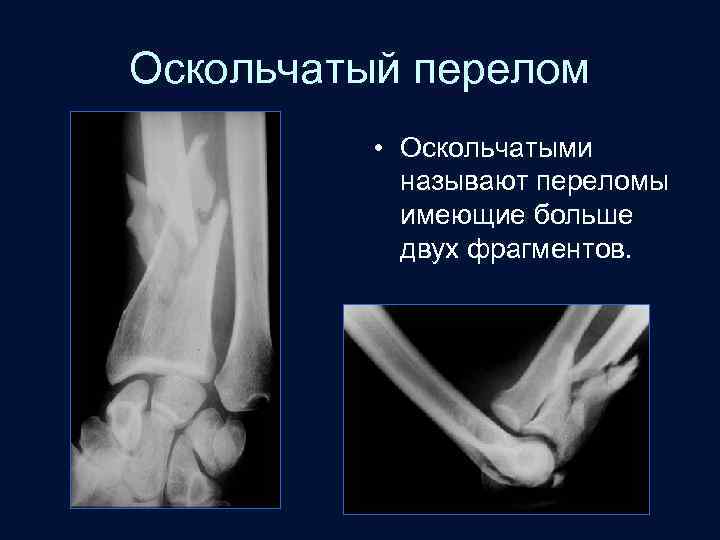

Оскольчатый перелом • Оскольчатыми называют переломы имеющие больше двух фрагментов.